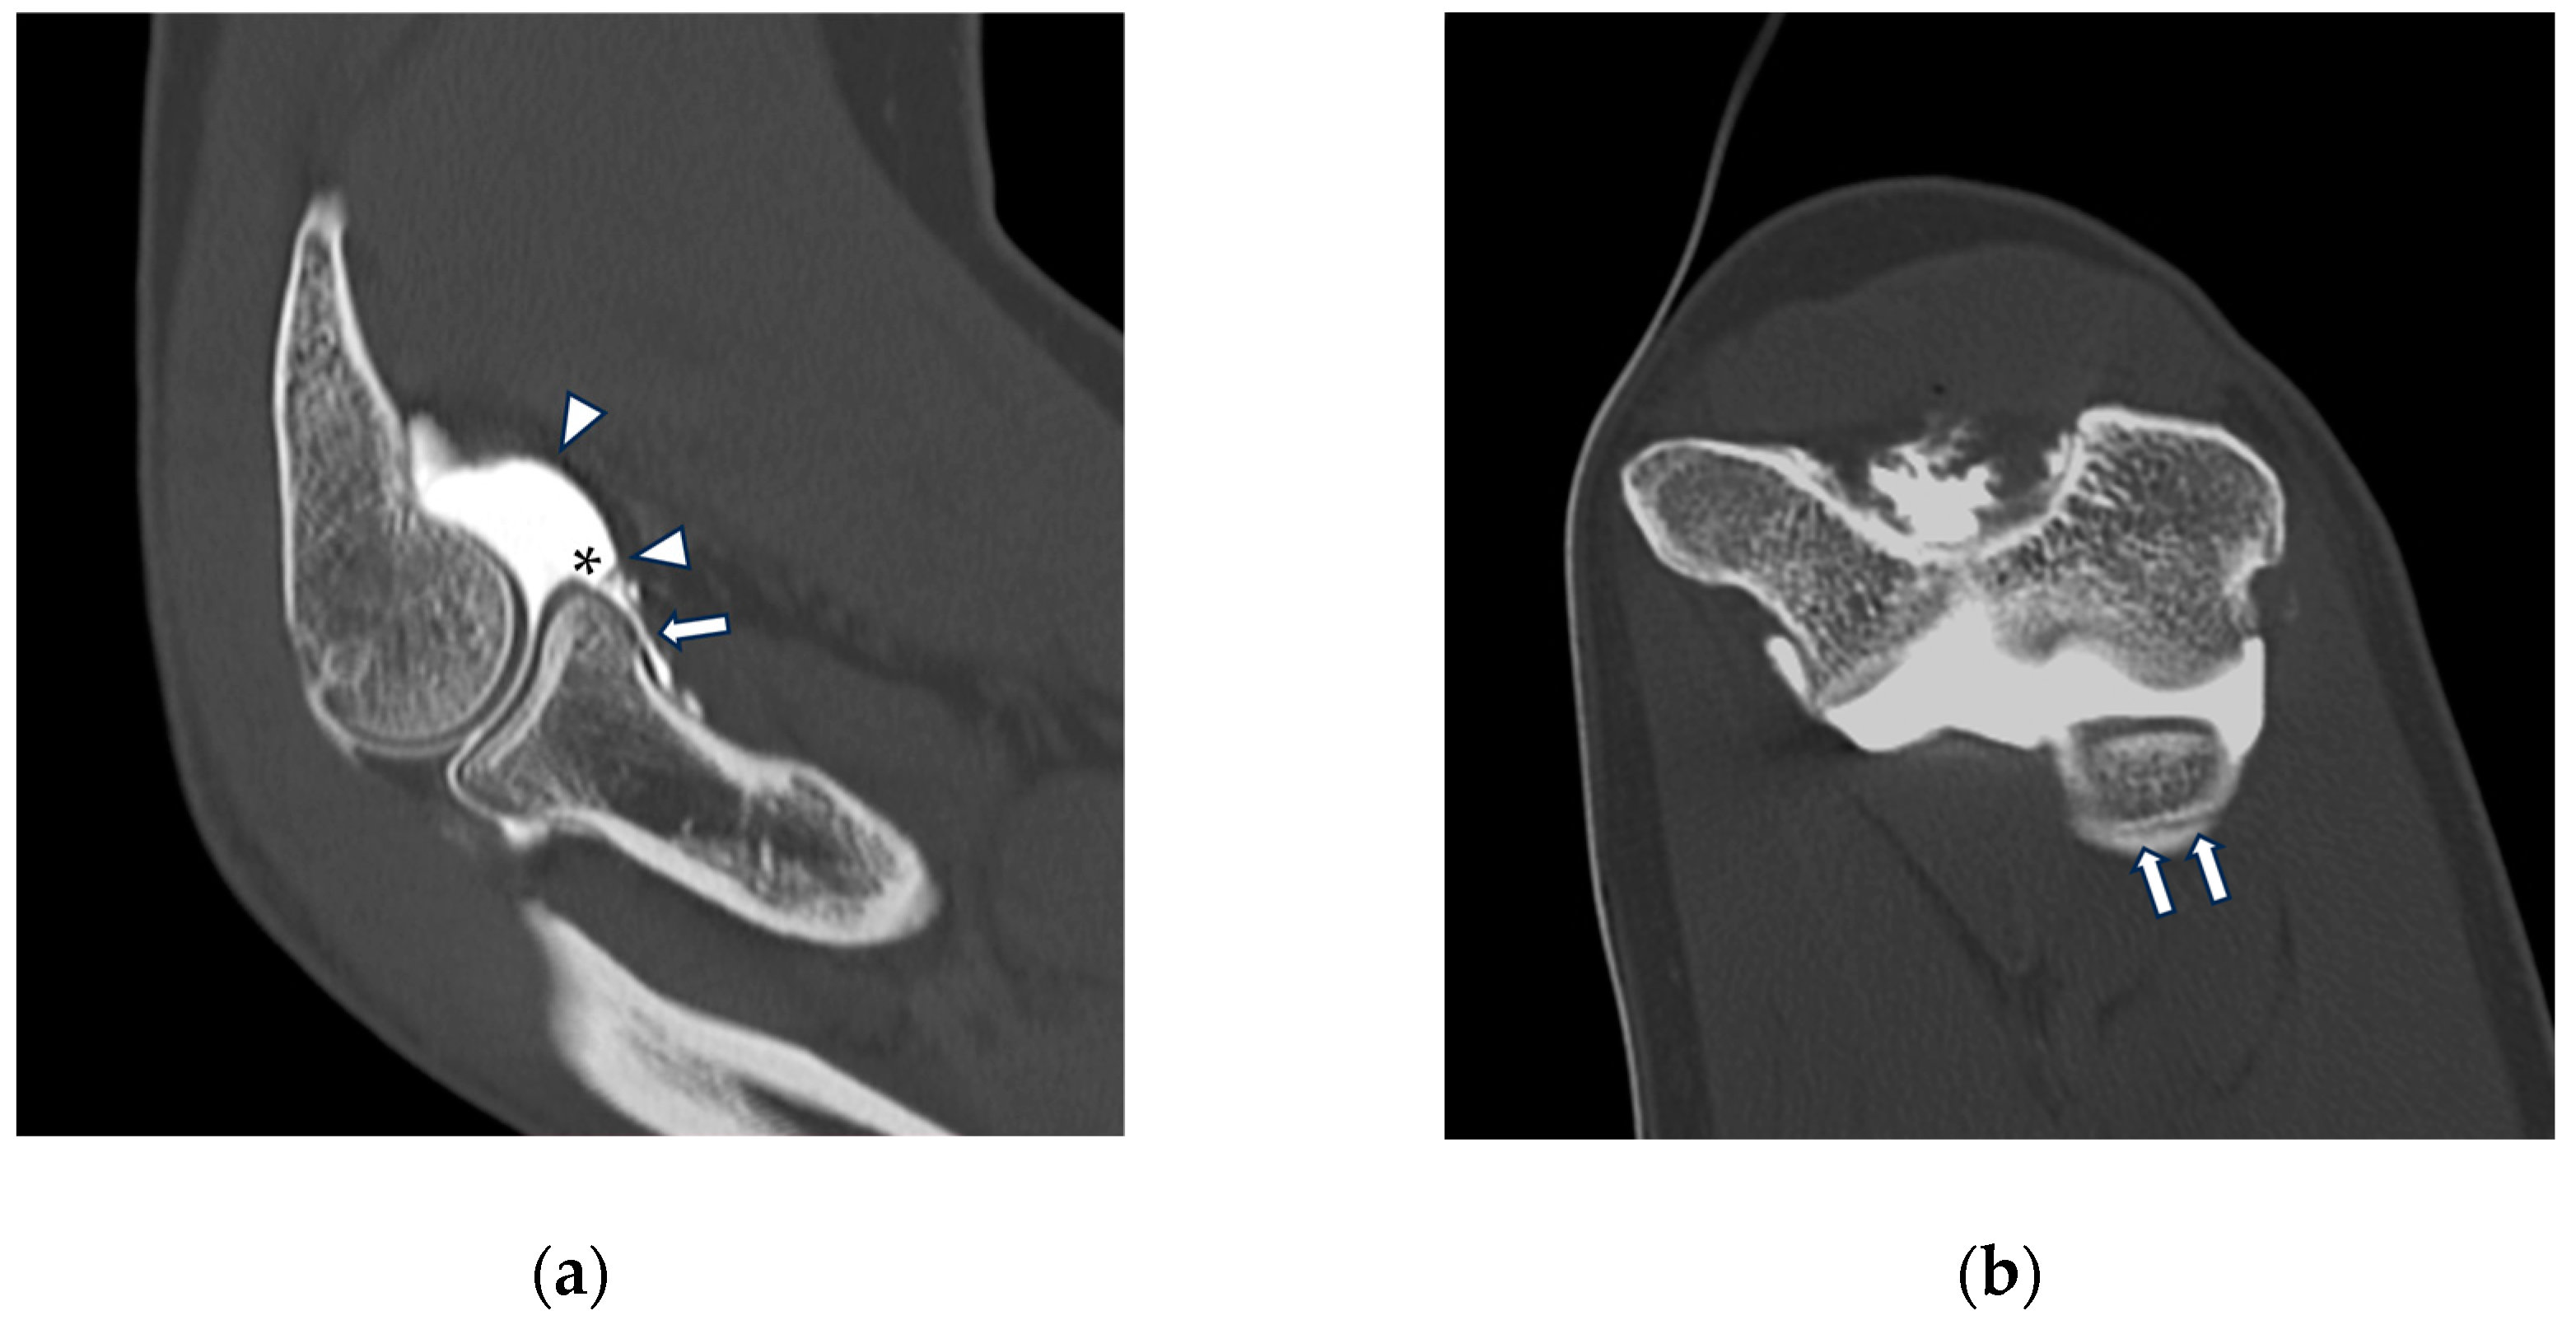

Figure 5.

CT arthrography of a patient with sequelae of traumatic elbow dislocation. (a,b) Coronal and axial images showing LCL laxity with subtle foci of contrast medium permeation due to ligament delamination (white arrowheads) and a loose body within a pathologically distended lateral recess (white arrow), as well as cartilage thinning and fraying of the lateral aspect of the capitulum humeri (yellow arrowhead). Post-traumatic deformity of the radial head can also be seen; (c) sagittal reformat shows a loose bony fragment posterior to the capitulum humeri (asterisk) and posterior synovial thickening (yellow arrow).

Figure 7.

CT arthrography of a patient with overuse-related lateral elbow pain. (a) Sagittal image shows pathological widening of the radio-humeral and radio-annular recesses (white arrowheads) due to ligamentous laxity—in particular, the annular ligament (white arrow) is displaced distally to the proximal half of the radial head side, which also shows anterior cartilage thinning and synovial thickening (asterisk); (b) the corresponding coronal reformat may aid in precise localization of the proximal extremity of the annular ligament, which can be visualized as a hypodense band anterior to the radial head (white arrows); in this instance, it shows marked distal displacement.